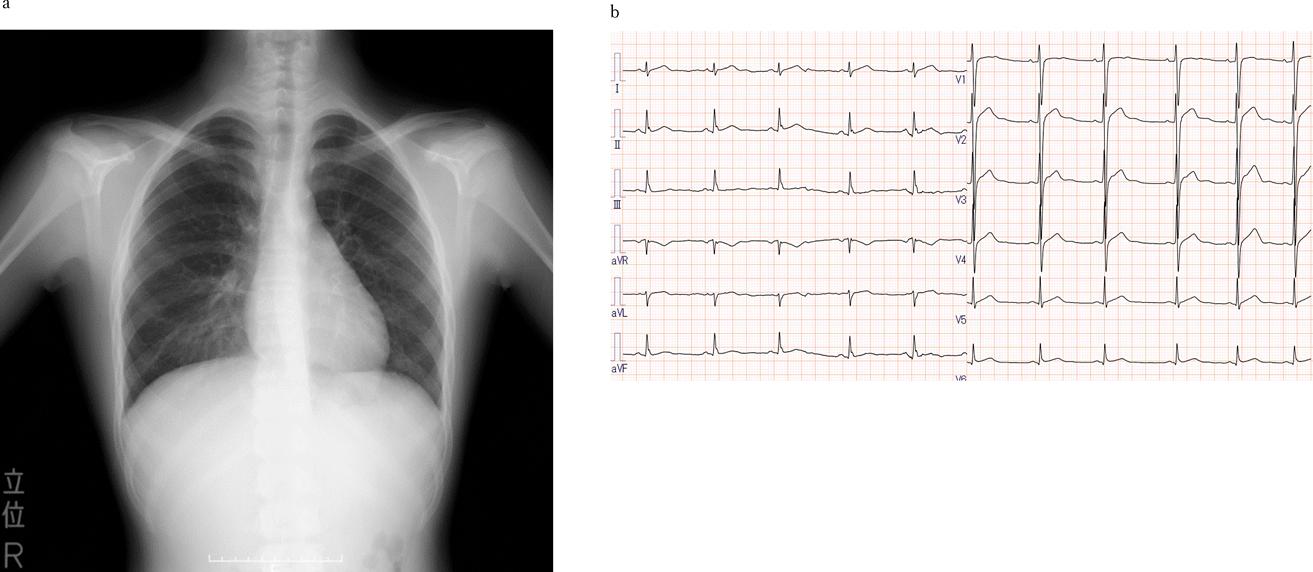

Fig. 3 CMR (Cardiovascular Magnetic Resonance Imaging) 6 months after onset (a, b: short axis view, c, d: three chambers view)

CMR shows late gadolinium enhancement on basal inferior lateral wall indicated by the arrows.

ワクチン接種から3日後の胸痛であり,心筋逸脱酵素の上昇を伴っていたことから,コロナワクチン接種後の心筋炎と診断した.入院時,バイタルサインの異常はなく,全身状態は保たれていたが,胸痛は持続していた.痛みは自制範囲内であったため鎮痛薬は使用せず,室内での安静を指示し,心電図・SpO2モニター管理で経過を観察した.胸痛は入院後数時間で消失し,以降再燃することはなかった.入院翌日の血液検査では,トロポニンI 6,465.4 pg/mL,CK/CK-MB 166/24 U/L, CRP 1.04 mg/dLと心筋逸脱酵素,炎症反応はともに低下した(Fig. 2).入院2日目の心臓超音波検査では,心収縮は良好であり,有意な弁逆流や心嚢液の貯留はなかった.その後も全身状態は良好であり,入院5日目の血液検査では,トロポニンI 44.6 pg/mL,CK/CK-MB 50/12 U/L, CRP 0.10 mg/dLと心筋逸脱酵素,炎症反応は正常化した.同日,階段昇降等の労作時にも症状の出現がないことを確認し,室内安静は解除した.12誘導心電図検査を入院中繰り返し行ったが,異常所見を認めなかった.外来で段階的に運動制限を緩和する方針の下,入院6日目に退院した.退院後も胸痛を含めた症状の出現はなく,退院後1か月の血液検査,心臓超音波検査では異常を認めなかった.12誘導心電図検査は入院時と変化なかった.また,発症後6か月のcardiovascular magnetic resonance imaging(以下CMR)では心基部下側壁に斑状のlate gadolinium enhancement(以下LGE)陽性所見を認めた.心筋浮腫は認めなかった(Fig. 3).

本症例では嘔吐を伴う強い胸痛と血清トロポニン上昇を認めたことから,日本小児循環器学会の小児期急性・劇症心筋炎の診断と治療の指針2)に則り,Acute mildの心筋炎に該当すると診断した.さらにCDCが提示しているコロナワクチン後心筋炎の基準3)に則り,血清トロポニン上昇と胸痛よりコロナワクチン後心筋炎と診断した.発症6か月後のCMRではLGE陽性所見を認め,診断を支持する所見と考えた.なお,ウイルス感染に伴う心筋炎の原因となるウイルスの分離検査やペア血清検査は先行感染を疑う呼吸器症状を認めなかったため施行しなかった.